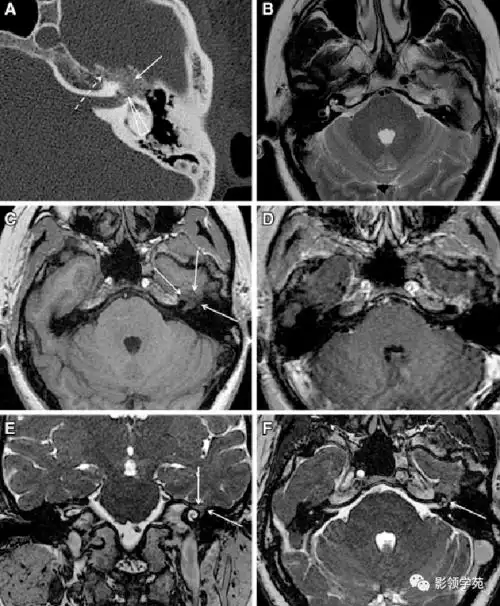

磁共振检查如3d-tof-mra,fiesta等,有助于明确责任血管和面神经之间的

面神经瘤的影像学特点